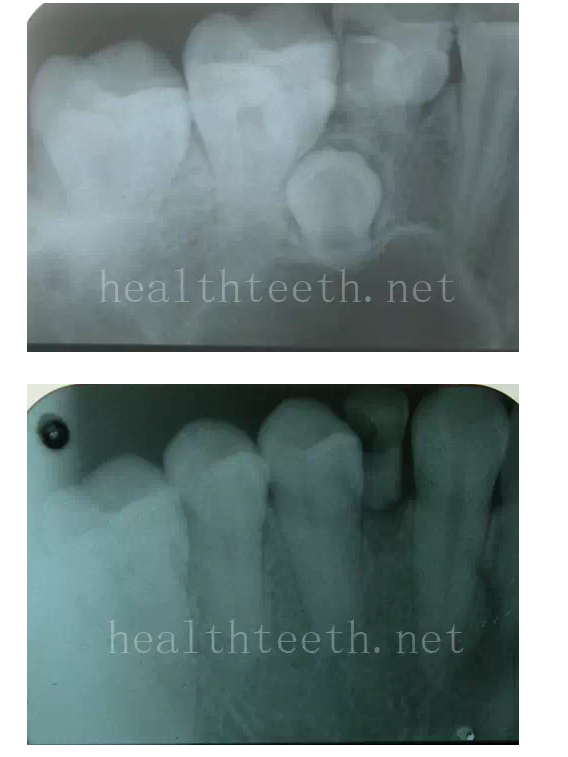

牙片顯示牙槽骨的垂直吸收

外院做的牙周固定,牙片顯示牙槽骨的水平吸收